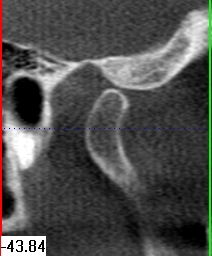

Im folgendem sehen Sie die Darstellung eines Teils des menschlichen Schädels mit Lokalisation des Nervkanales.

Coronalansicht |